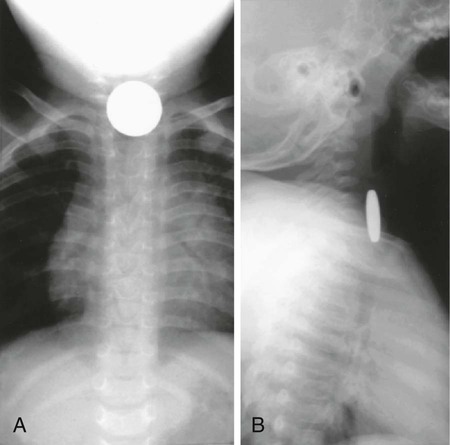

Evaluation of the child with a history of foreign body ingestion starts with plain anteroposterior radiographs of the neck, chest, and abdomen, along with lateral views of the neck and chest. The flat surface of a coin in the esophagus is seen on the anteroposterior view and the edge on the lateral view (Fig. 327-1). The reverse is true for coins lodged in the trachea; here, the edge is seen anteroposteriorly and the flat side is seen laterally. Disk batteries can look like coins (Fig. 327-2) and have a much higher risk of burns and necrosis (Fig. 327-3). Materials such as plastic, wood, glass, aluminum, and bones may be radiolucent; failure to visualize the object with plain films in a symptomatic patient warrants urgent endoscopy. CT scan with 3-dimensional reconstruction may increase the sensitivity of imaging a foreign body. Although barium contrast studies may be helpful in the occasional asymptomatic patient with negative plain films, their use is to be discouraged because of the potential of aspiration as well as making subsequent visualization and object removal more difficult.